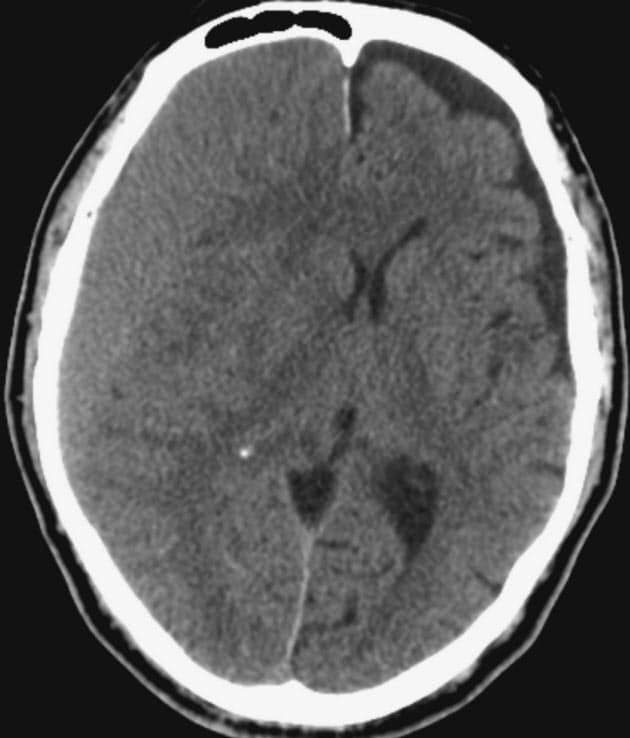

慢性硬膜下血腫 一般財団法人 富士脳障害研究所附属病院

急な頭痛やマヒ 認知症 慢性硬膜下血腫を疑って Nikkei Style

脳神経外科の病気 頭頸部外傷 病気の治療 徳洲会グループ

脳神経外科 診療科のご案内 国際医療福祉大学成田病院